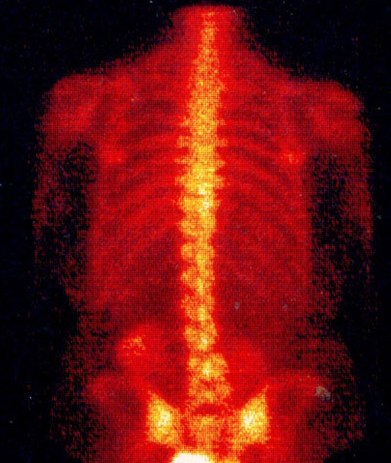

Сцинтиграфия костей - это черно-белое или цветное изображение, состоящее из штрихов и точек, благодаря которому врач может судить о состоянии костной ткани. Порядок проведения сцинтиграфии костей:

• Сцинтиграммы могут быть различными. Приборы регистрируют импульсы точками и штрихами, затем получаемая сцинтиграмма отпечатывается. С помощью другого метода сцинтиграфии делаются двухмерные снимки или запись на пленку. Части костей с наибольшим накоплением радиоактивных частиц - светлые (позитивные), а части, в которых процессы слабо выражены или вовсе не происходят - темные (негативные).

Имеются два вида опухолей костей. Первичные опухоли начинают расти в самой кости. У людей старшего возраста обычно обнаруживают вторичные опухоли, образовавшиеся вследствие метастазирования из других частей тела. Около 80% всех случаев метастазов в кости составляют метастазы в позвоночник. Поэтому при наличии в организме раковых изменений нередко выполняют и сцинтиграфию позвоночника.

Это исследование может быть выполнено и амбулаторно, однако обычно оно проводится в отделениях радиологии крупных больниц. Сцинтиграфия - это метод исследования, при проведении которого активированная частица ядра атакует специальный кристалл, вызывая свечение рентгеновских или гамма-лучей, и в тот момент происходит вспышка энергии, поглощение которой тканями тела человека различно. Эту разницу регистрирует специальный прибор. Пациенту вводят вещества, маркированные радиоактивными изотопами, которые при распаде излучают гамма-лучи. Эти нуклиды распределяются по всему организму человека. Спустя некоторое время на исследуемую часть тела человека накладывается прибор, регистрирующий гамма-лучи и «записывающий» сцинтиграмму. На сцинтиграмме костей опухоли — светлые, а здоровая костная ткань — темная.